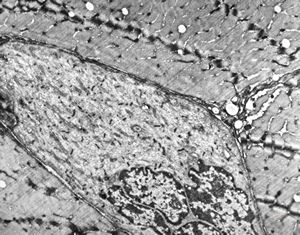

F,25y. | myopathy - atrophic and regenerating muscle cells